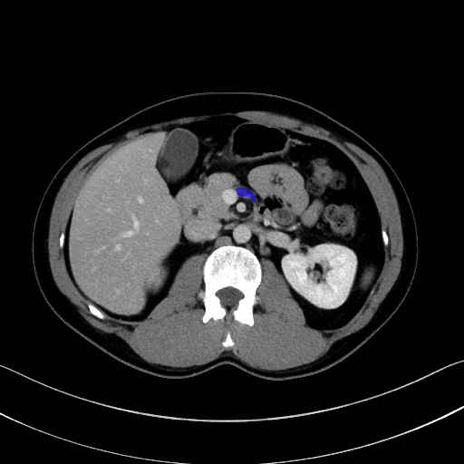

脾静脈の画像解剖

■起始:脾門で脾静脈枝が合流して本幹を形成。

■走行:膵体尾部の後面溝を右走し、膵頸部の後方で上腸間膜静脈(SMV)と合流して門脈を形成。

■主な流入枝:短胃静脈・左胃大網静脈・膵静脈、そして下腸間膜静脈(IMV)(変異あり)。